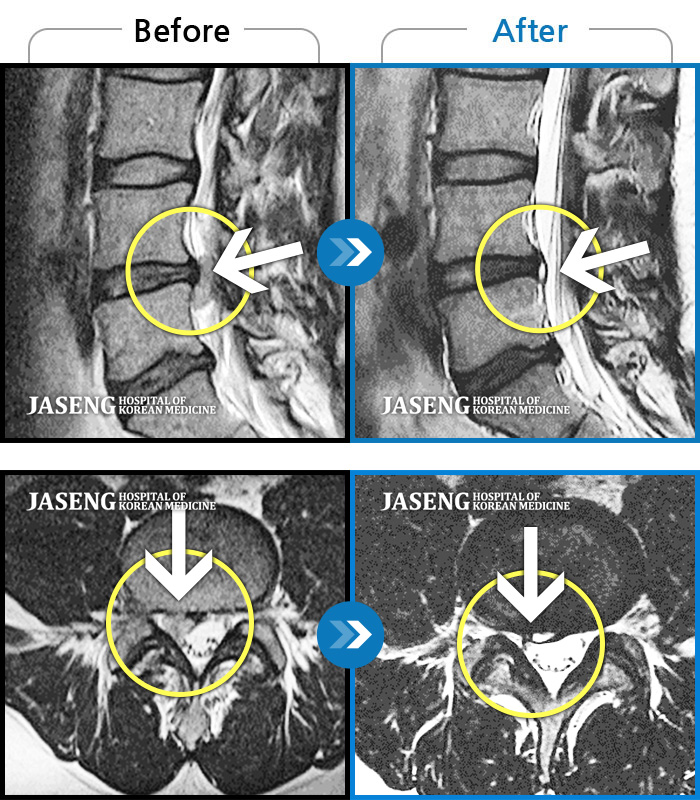

목디스크

부천 · 최요섭 원장

자고 일어난 후 발생한 극심한 후경부 통증 및 좌측 상완부의 저림

촬영시기

2024.01.11 ~ 2024.07.20

2024.07.26